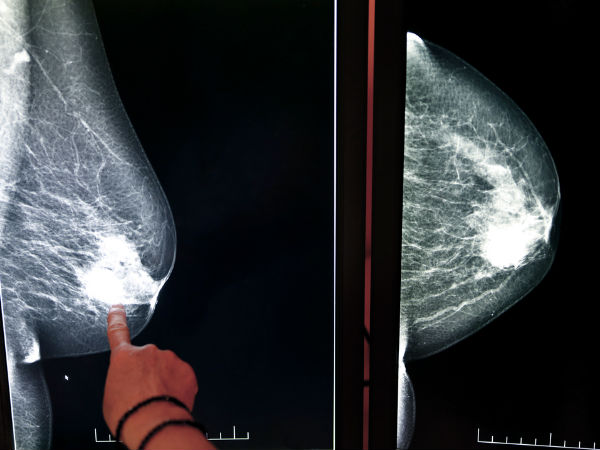

What causes dense breast tissue. So does a possible tumor. Women who have dense breast tissue have a higher risk of breast cancer compared to women with less dense breast tissue. 10242018 When radiologists look at your mammogram breast tissue will show up as black and white.

This type of tissue is often inherited but there are some factors that can influence dense breasts. 1272021 Cancers typically show up as small white spots or masses on a mammogram. Dense breast tissue also appears white on a mammogram.

Small areas of cancer can hide behind the dense tissue and its challenging to tell the difference. Young women have more circulating hormones. If you have a lower body mass index you are more likely to have dense breast tissue than women who are obese.

When the liver cant break down the bodys excess estrogen then the risk of estrogen-related breast cancer increases. On mammograms dense breast tissue looks white. Dense tissue can hide cancers.

7142020 Thats because dense breast tissue and some abnormal breast changes such as calcifications and tumors appear as white areas in the mammogram. Have a lower body mass index. In fact the possible association between dietary choices and breast density has become an emerging area of discussion among epidemiologists RDs and other respected researchers in the cancer field.